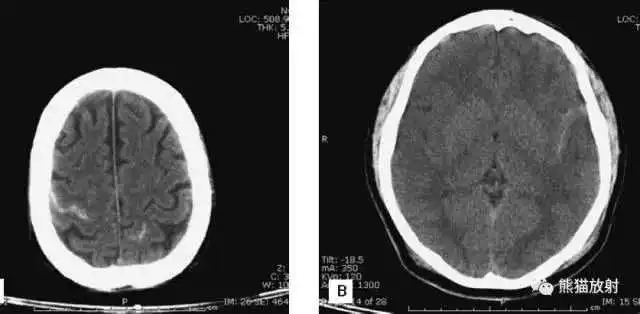

缺血性脑卒中

- 早期:脑水肿,灰白质分界模糊,脑沟消失;

- 中期:病变区域密度减低;

- 晚期:脑实质体积缩小。

A:陈旧性脑梗死,右枕叶体积缩小;

B:左枕叶急性脑梗死,灰白质分界模糊,脑沟消失;

另一患者:

C、D:亚急性期脑梗死,低密度,无明显占位效应。

▲

左侧大脑中动脉供血区脑梗死(亚急性期):

低密度,轻度水肿

缺血性脑卒中发作2-4天时,占位效应最明显。